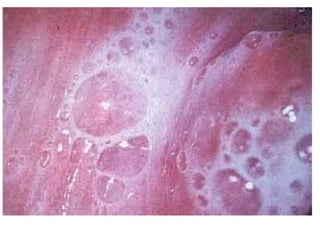

• A)Tegumentar ou cutânea:

• Cutânea: provoca lesões cutâneas

• Cutânea difusa: provoca metástases.

• Cutâneo-mucosa: destrói a mucosa nasofaríngea.

• B)Visceral: geralmente fatal e incurável, ataca

vísceras como fígado e baço.